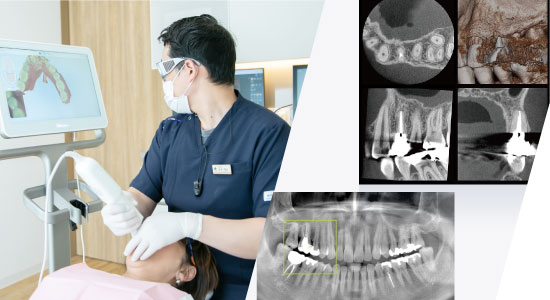

歯や骨の状態を的確に把握・判断するための歯科用3DデジタルCTや、より精密な型取りを短時間かつ快適に実現できる光学3Dスキャナー「iTero(アイテロ)」を導入しています。